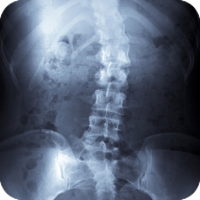

Like other health-care providers, we follow a standard routine to gain information about the patient. We consult, review the case history, conduct a physical examination, and we may request laboratory analyses and/or x-rays. Unlike other health-care providers, however, chiropractic physicians also conduct a careful analysis of the patient's structure and pay particular attention to the spine. We also ask you about your life- Do you eat well? Exercise at all? How do you deal with stress? Do you have children? What do you do for work? And so on.

Chiropractors have a term for misalignments: subluxations. A vertebral subluxation is a misalignment of the bones that protect the spinal cord. It's a leak in the roof. Or a kink in the wiring of your nervous system.  The severity of the subluxation can vary, and there are a number of potential contributing factors that can be physical, emotional, mental, or chemical. The subluxation can be caused by any number of incidents, from birth trauma to an auto accident to simple repetition or over-use.